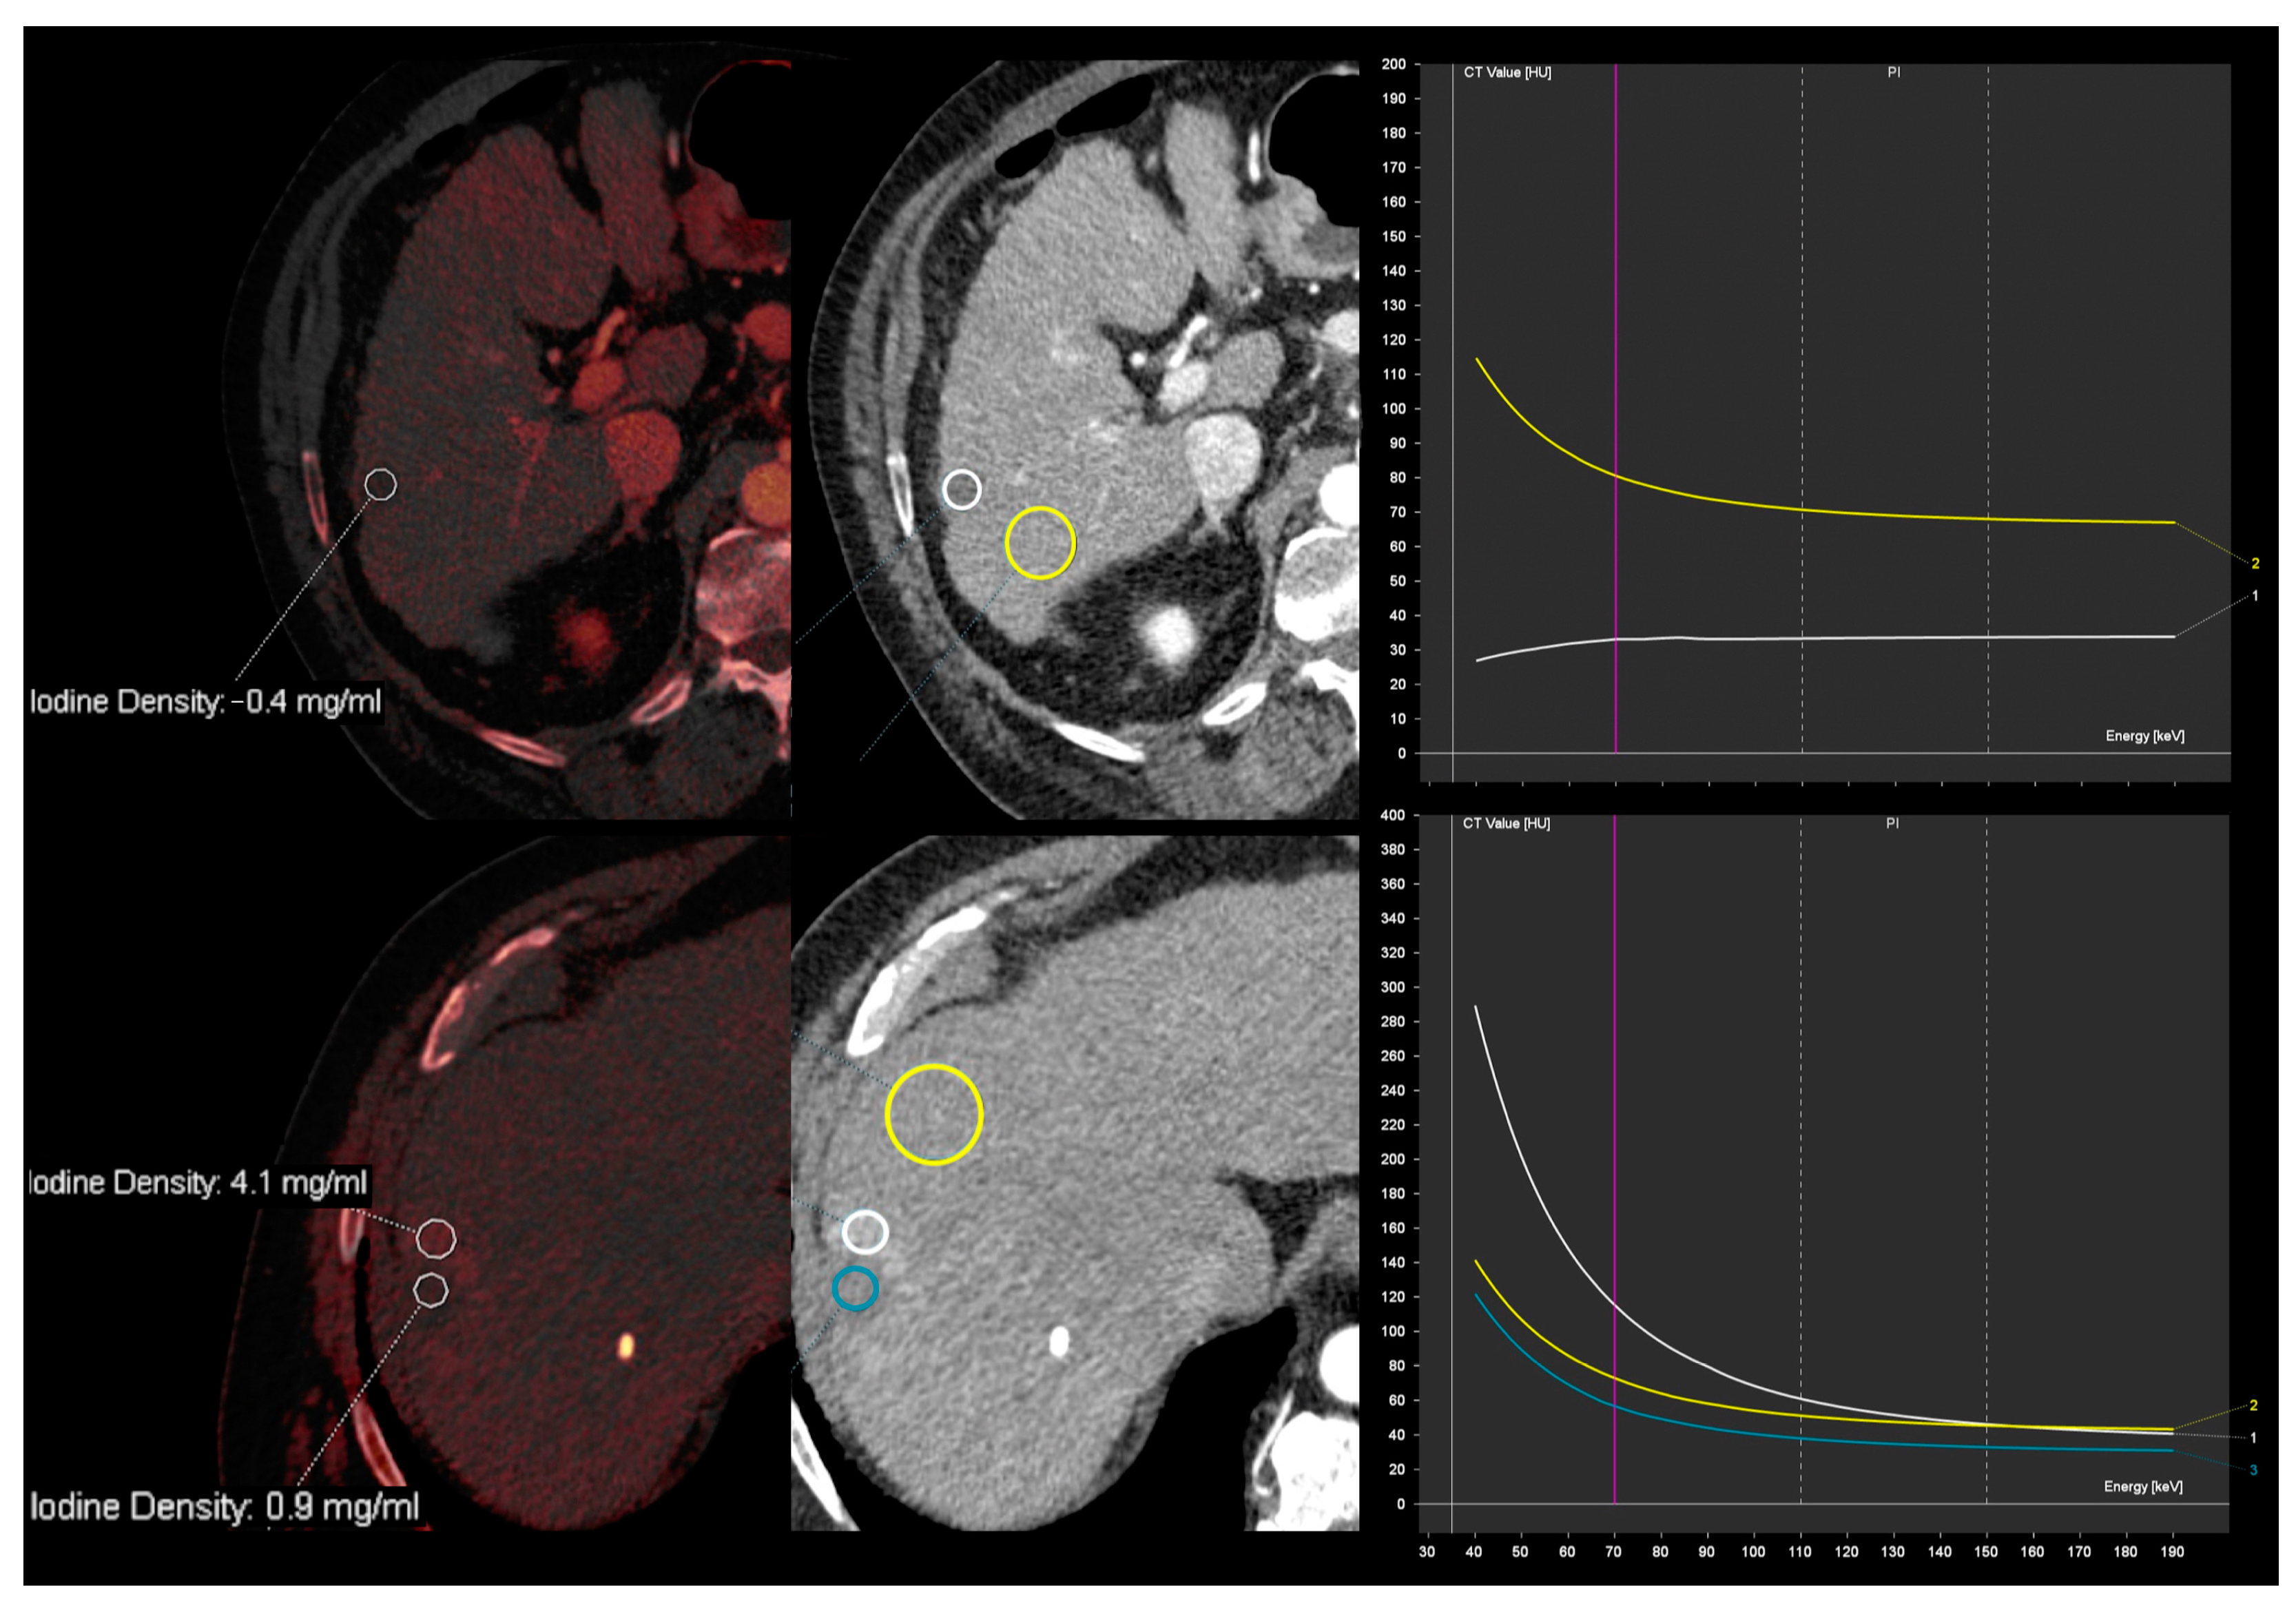

- Wang, Q.; Shi, G.; Qi, X.; Fan, X.; Wang, L. Quantitative analysis of the dual-energy CT virtual spectral curve for focal liver lesions characterization. Eur. J. Radiol. 2014, 83, 1759–1764. [Google Scholar] [CrossRef]